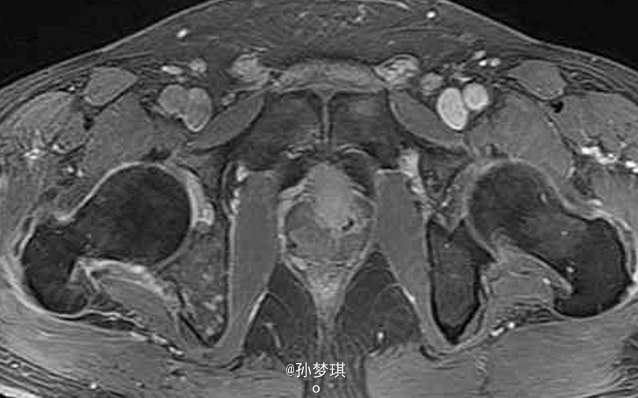

男,70岁,因排尿困难7年,加重3月前来就诊

患者除排尿困难外无其他不适症状 辅查MRI,T2W示前列腺外周带正常高信号环中断,信号不均匀升高;增强T1WI示前列腺外周带偏右侧增厚,右侧坐骨支不均匀强化